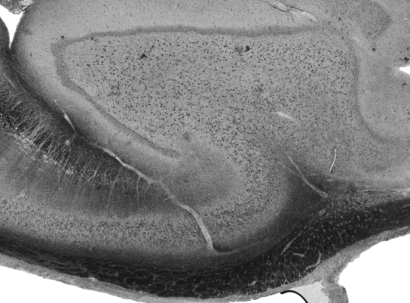

Understanding the cortical organization of the human brain requires interpretable descriptors for distinct structural and functional imaging data. 3D polarized light imaging (3D-PLI) is an imaging modality for visualizing fiber architecture in postmortem brains with high resolution that also captures the presence of cell bodies, for example, to identify hippocampal subfields. The rich texture in 3D-PLI images, however, makes this modality particularly difficult to analyze and best practices for characterizing architectonic patterns still need to be established. In this work, we demonstrate a novel method to analyze the regional organization of the human hippocampus in 3D-PLI by combining recent advances in unfolding methods with deep texture features obtained using a self-supervised contrastive learning approach. We identify clusters in the representations that correspond well with classical descriptions of hippocampal subfields, lending validity to the developed methodology.